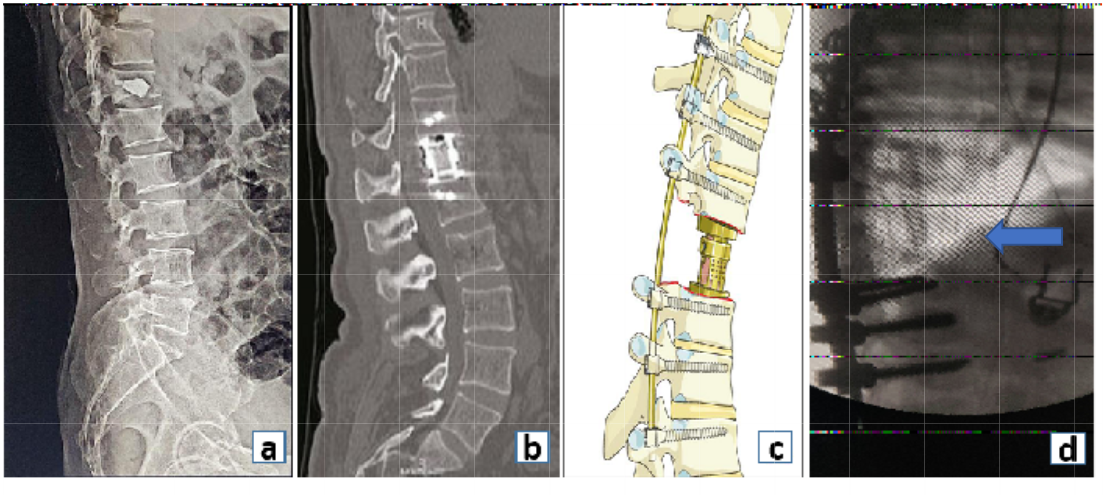

According to the Dennis column theory, spine is divided into three columns namely anterior, middle and posterior. Reconstruction refers to the construction of the damaged/deficient columns of the spine. Discussion begins with the fact that spine is a two column structure with anterior and middle column of the three column theory collapsed together into one column.

In a healthy spine, 80% of the load is carried by the anterior column while the remaining 20% is carried by the posterior column. Hence reconstruction of the anterior column in a defect assumes significance (Fig. 11).

Figure 11: Reconstruction of the anterior column with (a) bone cement, (b) cylindrical expandable cage, (c) pictorial image demonstrating expandable cage used for anterior column reconstruction, (d) and use of fibular strut graft (blue arrow) for anterior column reconstruction.

The destruction of a particular spinal column can be multifactorial. It can be due to malignancy, traumatic spinal fractures, spinal infections and osteoporotic fractures to name a few.

Comminuted unstable thoracolumbar body fractures, with severe comminution of anterior column can overburden the posterior instrumentation and lead to failure. Corpectomy defects due to these fractures or tumors require an anterior reconstruction procedure. This can be achieved with strut grafts, femoral allografts, cylindrical cages, expandable cages or bone cement. The requirement of an anterior reconstruction procedure in severely comminuted thoracolumbar fractures has been well documented and quantified by the McCormack Load Sharing Classification [14].